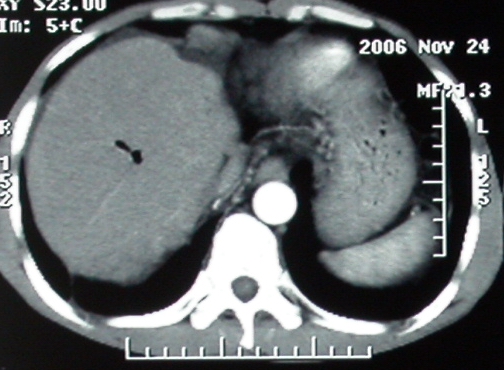

标题: CT5432:上腹隐痛、饱胀、消瘦2-月(尾状叶肝癌)。 [打印本页]

标题: CT5432:上腹隐痛、饱胀、消瘦2-月(尾状叶肝癌)。

男,57岁。

平扫